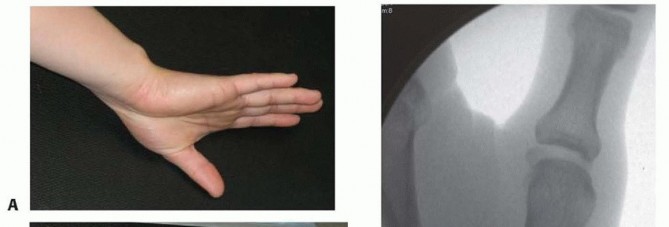

Clinical Evaluation and Diagnostic Imaging

The clinical evaluation must begin with a detailed history, focusing on the mechanism of injury, occupational demands, and hand dominance. Physical examination will typically reveal profound localized tenderness, swelling, and ecchymosis around the thenar eminence. Palpable instability or a visible "shelf" deformity at the CMC joint strongly suggests dorsal subluxation of the metacarpal shaft. A rigorous neurovascular examination is mandatory, with specific attention paid to the superficial radial nerve and the palmar cutaneous branch of the median nerve, both of which are at risk during surgical approaches to this region.

Our imaging protocol must be exhaustive to provide a three-dimensional understanding of the fracture morphology. Standard hand radiographs are insufficient due to the unique 30-degree pronated position of the thumb relative to the rest of the carpus. A True AP View of the Thumb CMC Joint (Robert's view) is obtained with maximal forearm pronation, placing the dorsum of the thumb flat on the cassette. This optimizes visualization of the joint space and the critical ulnar fragment. The True Lateral View (Billing and Gedda) is achieved with the hand pronated 20 degrees and the thumb flat on the cassette, with the X-ray beam tilted 10 degrees from vertical in a distal-to-proximal direction.

Closed Reduction and Percutaneous Pinning (CRPP)

CRPP is the treatment of choice for classic Bennett fractures where the volar-ulnar fragment is too small to reliably accept a lag screw, yet the joint can be anatomically reduced closed. The reduction maneuver is highly specific, designed to counteract the deforming forces of the APL and Adductor Pollicis. Longitudinal traction is applied to the thumb, followed by palmar abduction and pronation. Direct pressure is then applied to the dorsal-radial aspect of the metacarpal base, effectively pushing the shaft back into the anatomic cradle of the intact volar-ulnar fragment.